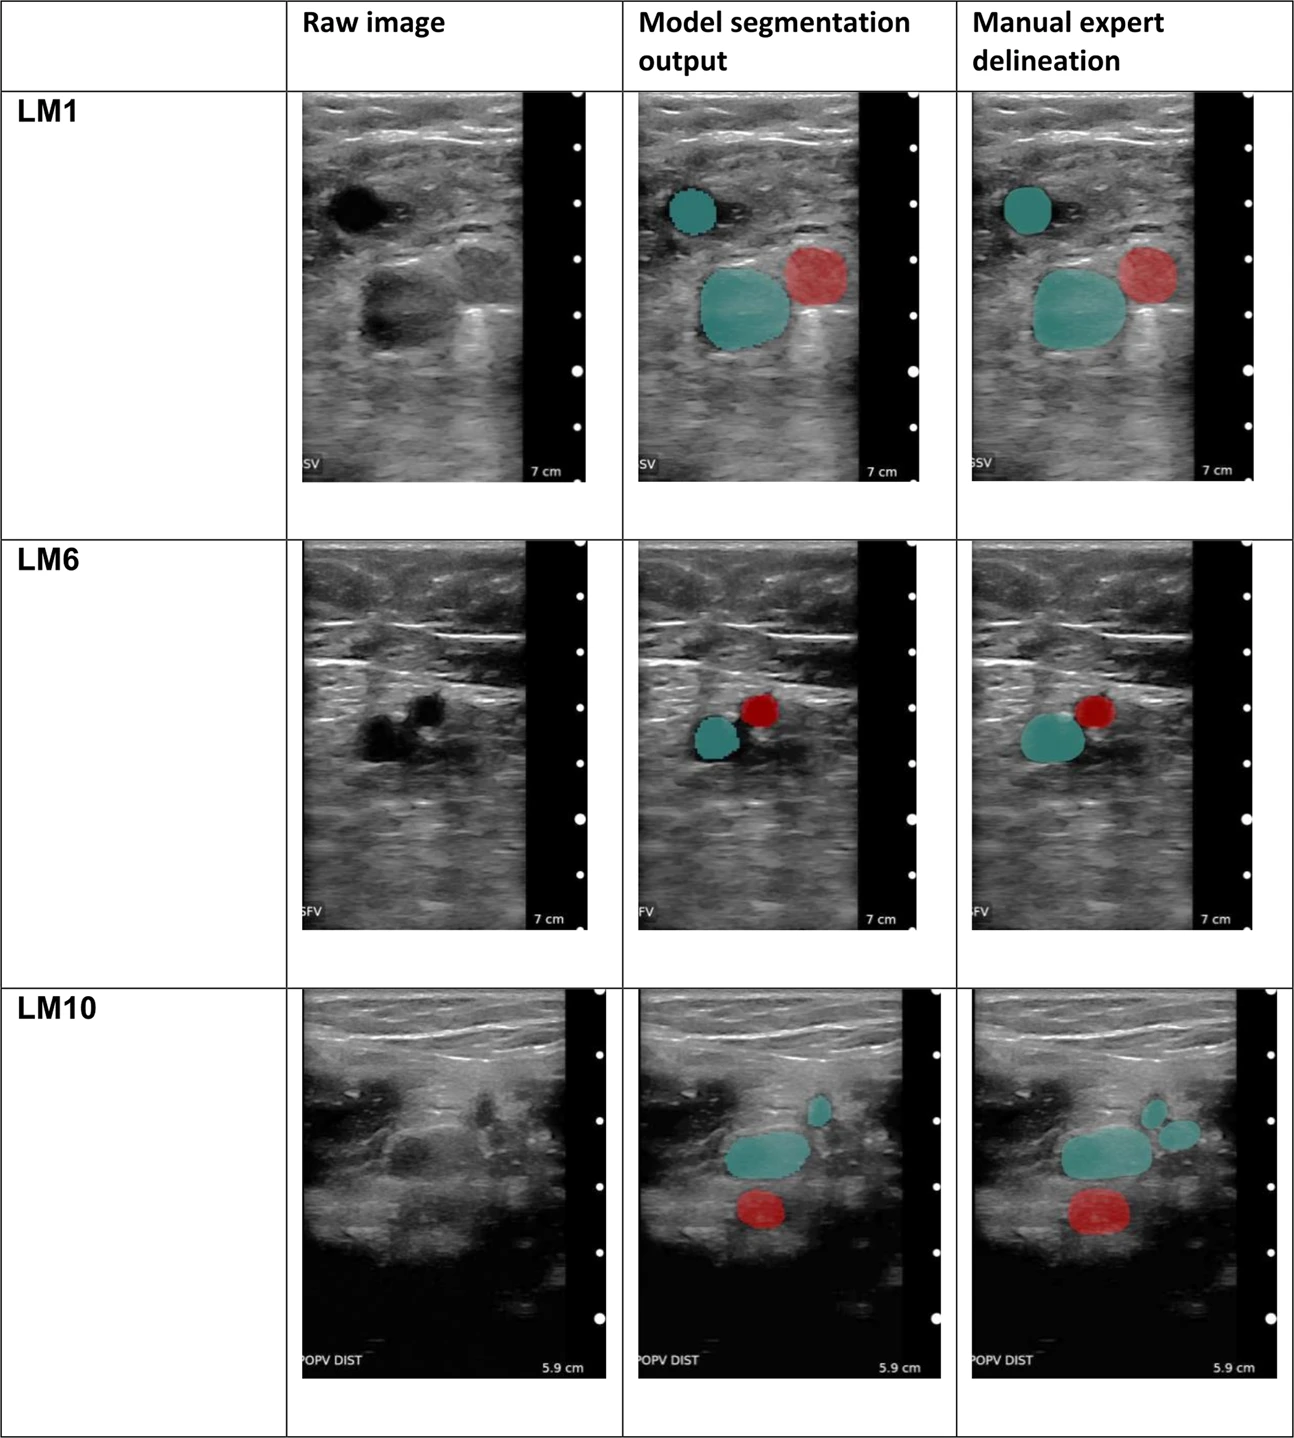

A blood clot called deep vein thrombosis (DVT), which is most frequently detected in the leg and can result in a catastrophic pulmonary embolism (PE). In a pre-clinical investigation of [23] the authors gather photos and look into a deep learning method for automatically interpreting compressed ultrasound images. Our technique assists non-specialists in identifying DVT and offers direction for free-hand ultrasonography. We use ultrasound films from 255 volunteers to train a deep learning system, and we use 53 prospective NHS DVT diagnostic clinic patients and Thirty prospective German DVT hospital patients as our sample size for evaluation.Through all compressions, the segmentation is strong which is shown in 3. To rule out DVT, the venous region is assessed for total compressibility.